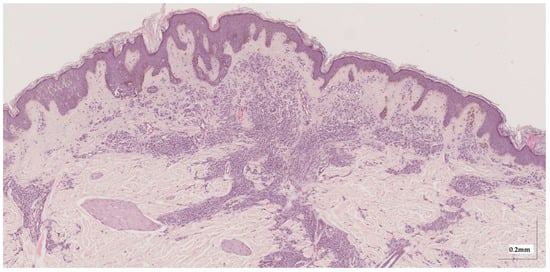

Appendix A. Selected Cases Studies’ HE Histopathological Images (Limited to OCT FOV)

| Melanoma in-situ (MIS) Case 2 | Localization: left chest |

![]() | ![]() |